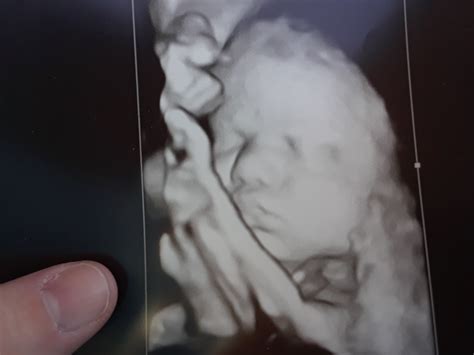

• down syndrome 3d ultrasound pictures

• down syndrome ultrasound 20 weeks